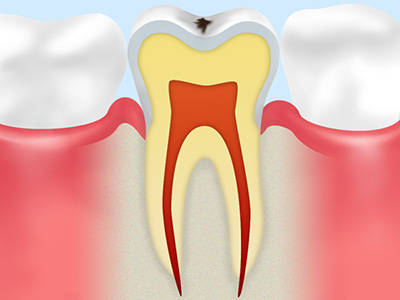

C3

象牙質の内側にある神経まで虫歯菌が到達した状態です。歯冠部の大部分が溶けてしまい、神経が露出しているため何もしていなくても激しく痛みます。この段階になったら、虫歯菌に感染した神経を取り除く根管治療根管治療を行い、被せもので歯の機能を回復させる治療を行います。

C4

完全に歯冠部が溶かされてしまった状態です。神経も壊死してしまうため一時的に痛みはなくなりますが、歯周組織の炎症が進むにつれて膿が出るようになると再び激しく痛みます。この段階になると、歯を残すことが難しいこともあります。どうしても保存出来ない場合は抜歯になり、入れ歯やインプラントなどで歯の機能を回復させる治療を行います。